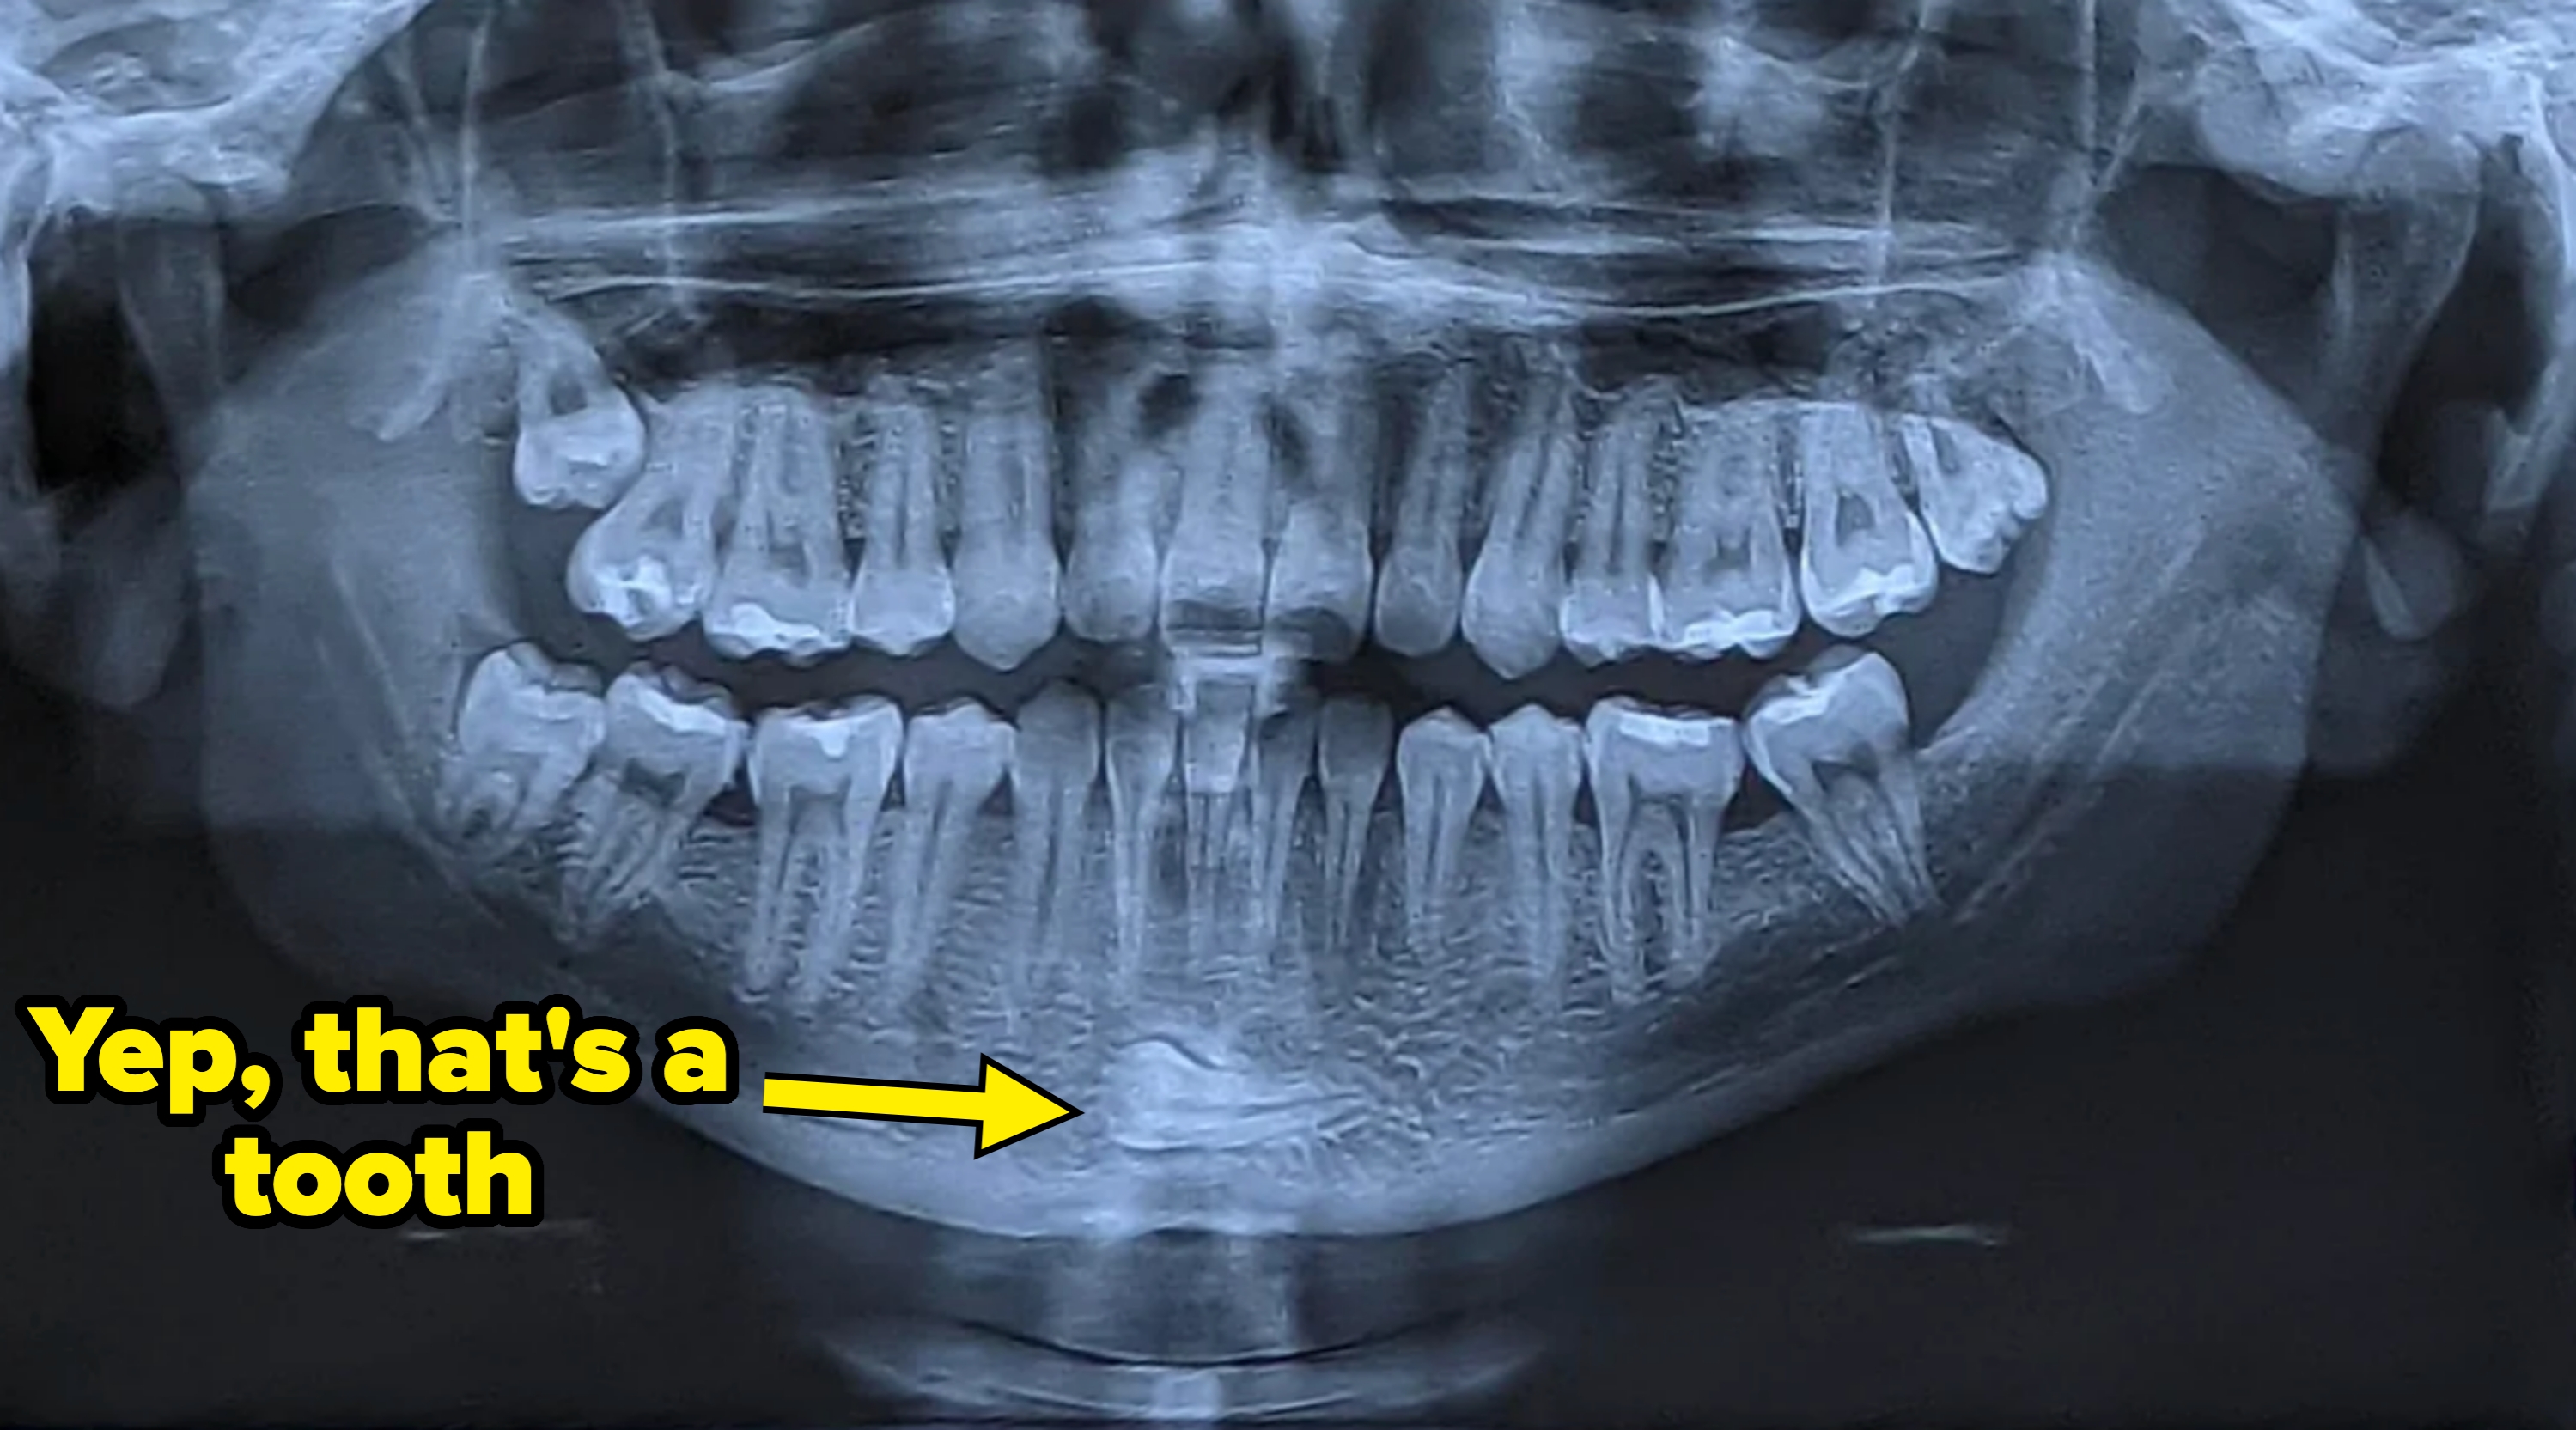

25.Teeth can be in places where they really shouldn’t be.

26.And some people have multiple extra teeth in places they shouldn’t be.